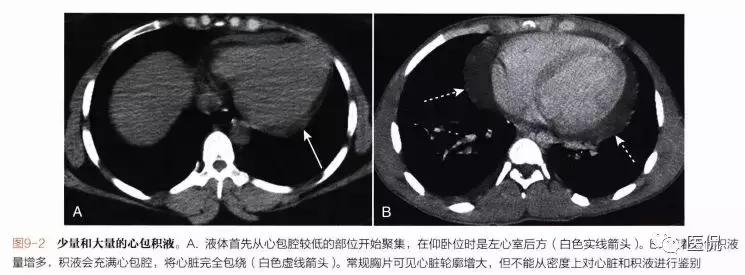

■液体异常积聚开始于心包腔较低位置,即在仰卧位时的左心室后方(图9-2A)。

■随着心包积液量增多,积液会沿着右心边缘积聚直至充满心包腔,将心脏完全包绕(图9-2B)。

■常规平片在心包积液诊断上不具有优势,示少量的心包积液。目前心脏超声是心包积液检查CT可以显的首选。